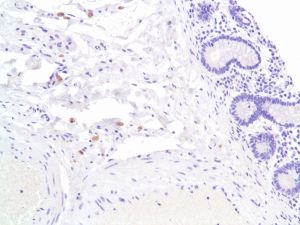

F4/80 (SP115)

Mouse EGF-like module-containing mucin-like hormone receptor-like 1 (EMR1) or cell surface glycoprotein F4/80 is a cell surface glycoprotein and a member of the EGF TM7 family of proteins. It shares 68% overall amino acid identity with human EGF-module-containing-mucin-like hormone receptor 1 (EMR1). Expression of F4/80 is heterogeneous and is reported to vary during macrophage maturation and activation. The F4/80 antigen is expressed on a wide range of mature tissue macrophages including Kupffer cells, Langerhans, microglia, macrophages located in the gut lamina propria, peritoneal cavity, lung, thymus, bone marrow stroma and macrophages in the red pulp of the spleen. F4/80 expression has also been reported on a subpopulation of dendritic cells but is absent from macrophages located in T cell areas of the spleen and lymph node. The ligands and biological functions of the F4/80 antigen have not yet been determined but recent studies suggest a role for F4/80 in the generation of efferent CD8+ regulatory T cells.